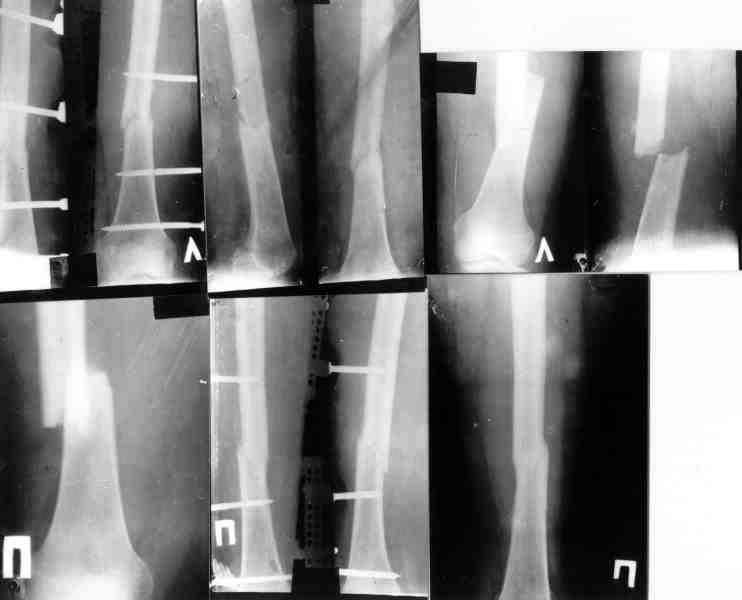

Ув. Михаил Викторович. Вы писали, что около 10 лет применяете стержневые аппараты, но они не обладают репозиционными возможностями. У нас был

разработан такой аппарат (авторы: Тауфик Амро, Сушко Геннадий Александрович (ученик Илизарова)). Манипулируя узлами данного аппарата возможно закрыто устранить любые смещения, за исключением ротационных.

Высылаю

видеофайл (несколько неудачный, но смысл понятный) - Аппата Амро широко применяется в Запорожье, Мелитополе, Приморске.

Изготовить его особого труда не составляет. У нас в Приморске своими силами мы изготовили 10 таких. Если Вас это заинтересует - вышлю чертежи, и др. информацию.